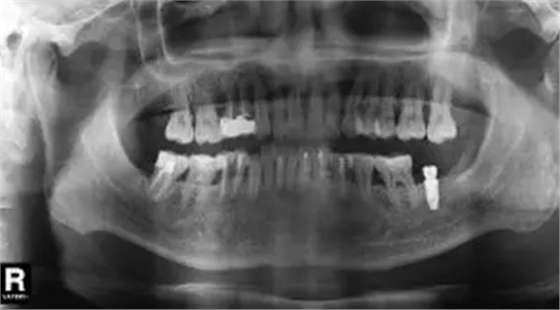

圖6 拔除47前曲面體層片

臨床檢查47面見大面積充填物,冠近遠中折裂,叩痛(+),松動度(-),牙齦(-)。曲面體層片示46髓腔內及根管見高密度影像,根尖未見明顯陰影(圖6)。

診斷47折裂牙,治療計劃

微創(chuàng)拔除47后,植入骨粉膠原塞(圖7~9);3個月后CBCT分析骨質;行47種植牙修復術。